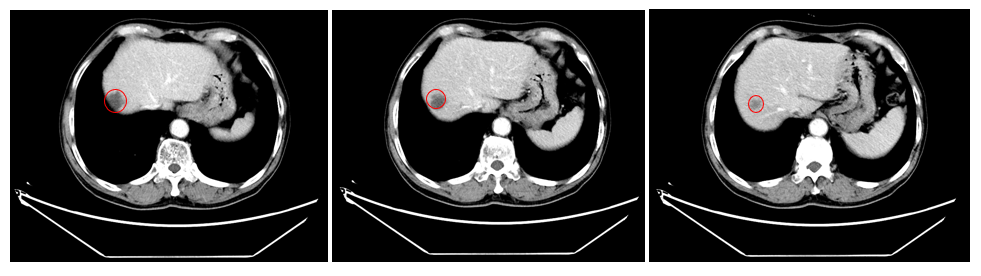

历经规范的SBRT立体定向放疗后,刘某复查CT结果传来捷报:与放疗前相比,肝内转移肿瘤病灶出现明显缩小,治疗效果确切,病情得到有效控制!

(▲放疗后CT图像)